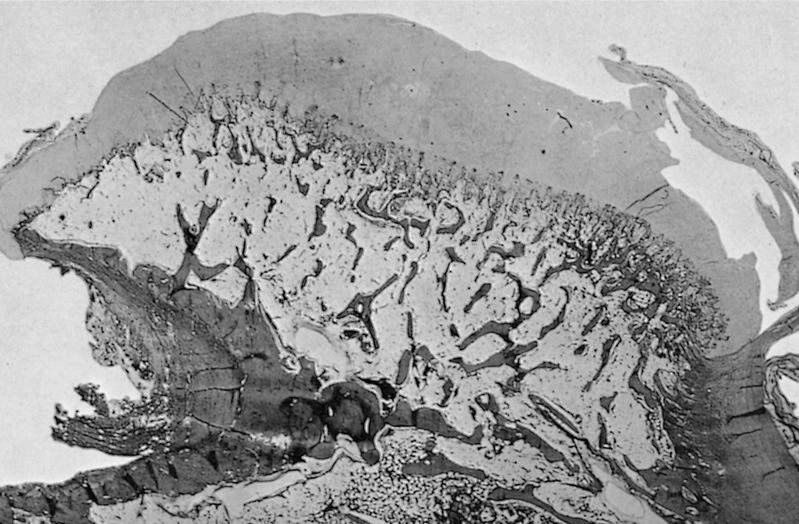

Microscopic (histologic) description

- Cap composed of mature hyaline cartilage with overlying fibrous perichondrium

- In young patients, transition between bone and cartilage cap resembles growth plate, showing endochondral ossification into mature bone; cartilage cap diminishes and may essentially be absent in older adults

- Marrow elements may be present within bony stalk; marrow space / cancellous bone contiguous with that of the native bone

Microscopic (histologic) images